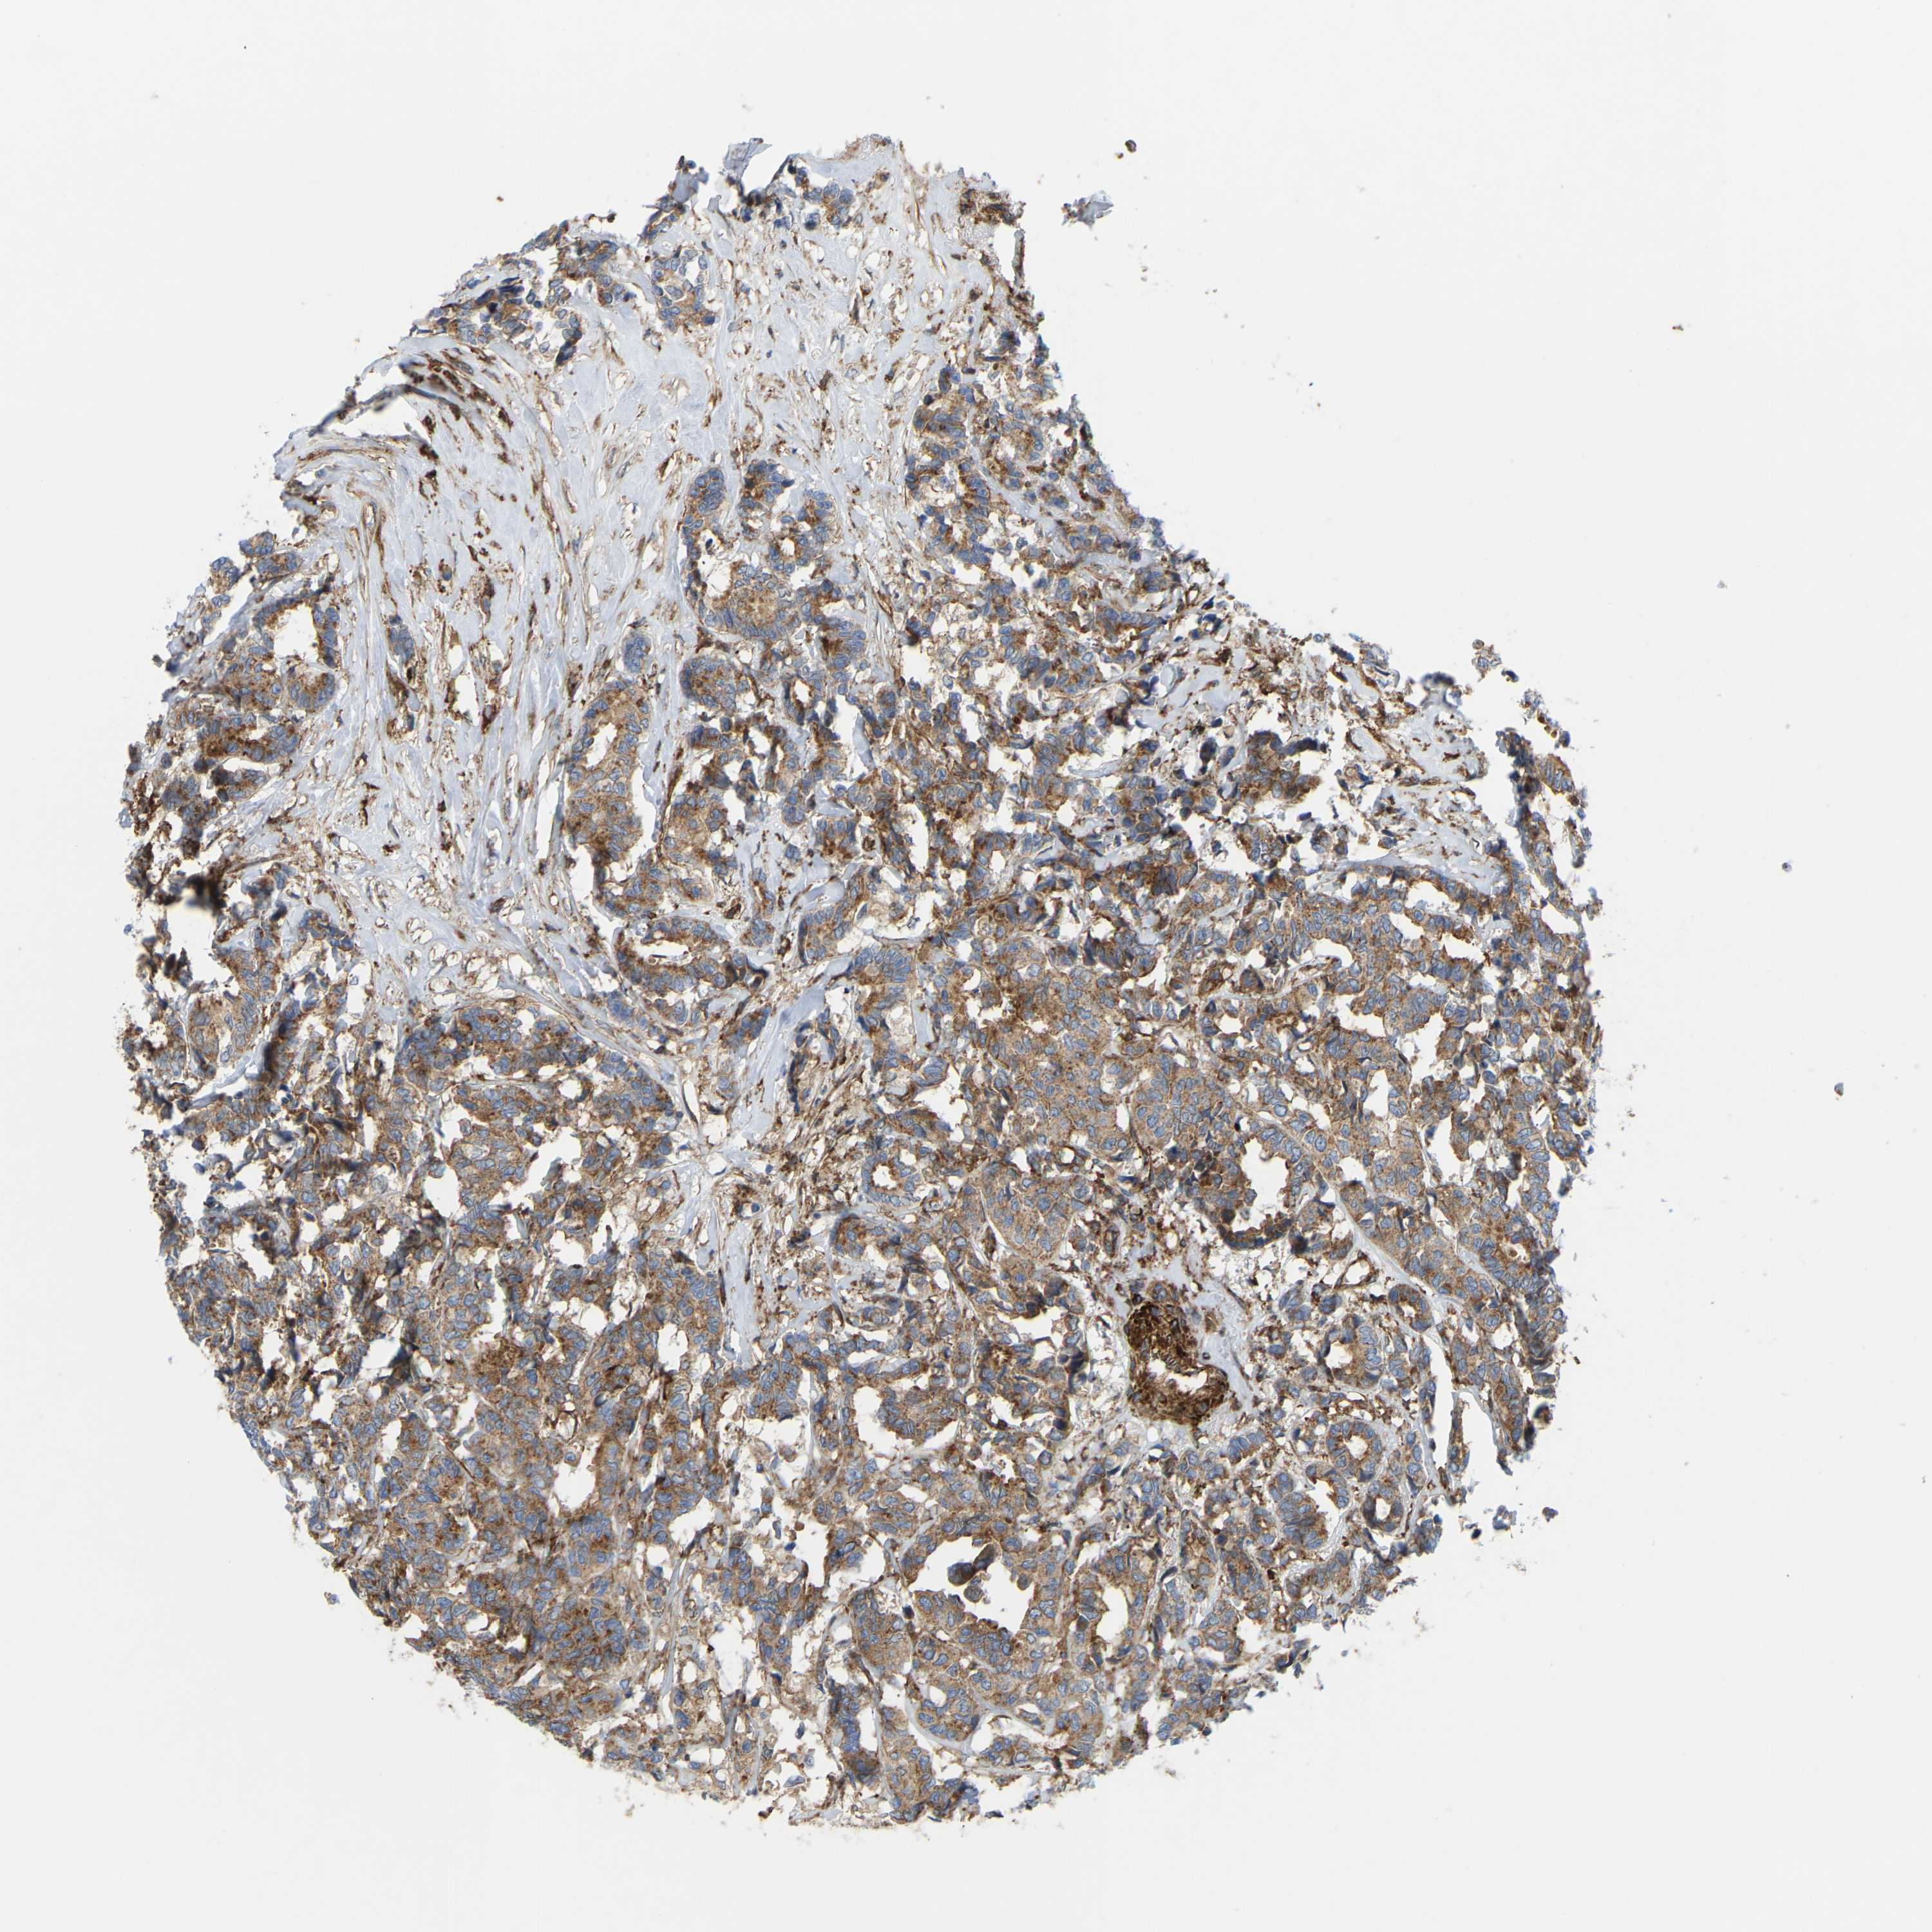

CANCER BREAST CANCER Show tissue menu

BRCA TCGA BRCA VALIDATION PROTEIN EXPRESSION

ANTIBODIES

AND

VALIDATION